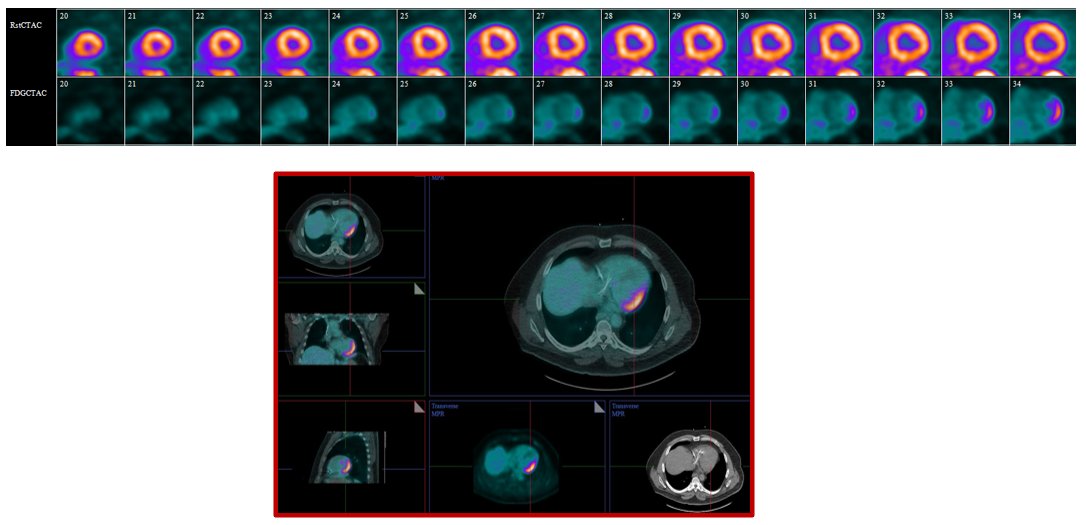

49-year-old with frequent VEs underwent rest Rb-82 imaging and 24-hr. carbohydrate-restricted diet for F-18 FDG PET to exclude cardiac sarcoidosis. Beta-hydroxybutyrate level < 0.2 mmol/L (normal > 0.3 mmol/L). What is your interpretation? Vote below.

A new @PennCardiology #clinicalcase aimed to: 👉formulate diagnoses of persistent FDG uptake on serial PET imaging 👉understand the mechanistic rationale of alt. causes that may result in persistent FDG uptake https://t.co/ZJ8UQxe534 #Aneurysm #CVImaging @mkvidula @pacoebravo

A new @pennmedicine study investigated the effect of immunosuppressive 🩺 therapy & biopsy 💉 status to achieve CTR, PTR or NR on myocardial FDG-PET/CT. Learn more➡️ https://t.co/H5RollrTyg @senthil_selv @mkvidula @leegoldbergmd8 @pacoebravo

Through #cvNuc FDG-PET, a favorable response was more common when using moderate-to-high intensity steroids. After nearly 5 years, biopsy-proven and with preserved systolic function were less likely to experience adverse outcomes. https://t.co/b3AZsOdPTe #JACCIMG #Sarcoidosis